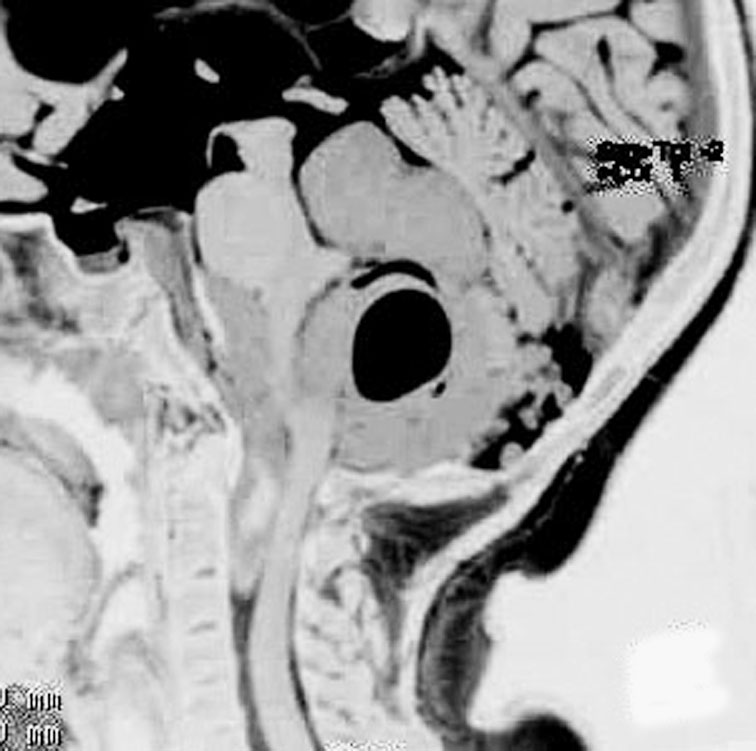

青年に発生したものです。かなり分化度の高い延髄背側 ovex 発生の上衣腫です。境界が明瞭なのですが,実際に側方(延髄小脳脚槽)で椎骨動脈や後下小脳動脈,下位脳神経に癒着しているので剥離は必ずしも容易ではありません。この例では幸い全摘出できました。

摘出した標本のHE染色です。左側ではperivascular pseudorosette(血管周囲の無核野)がみられ,右側ではependymal tube (ependymal canal) が認められます。

左がGFAP染色、右がMIB-1(Ki-67)染色です。 GFAPは腫瘍血管の周囲の無核野に強陽性です。MIB-1 labelling index が1%以下であり,この上衣腫の増殖能が極めて低いことを示しています。このような高分化型で増殖能の低い上衣腫は脊髄髄内には多いのですが,脳では珍しいものです。ovex中心上衣腫にみられます。